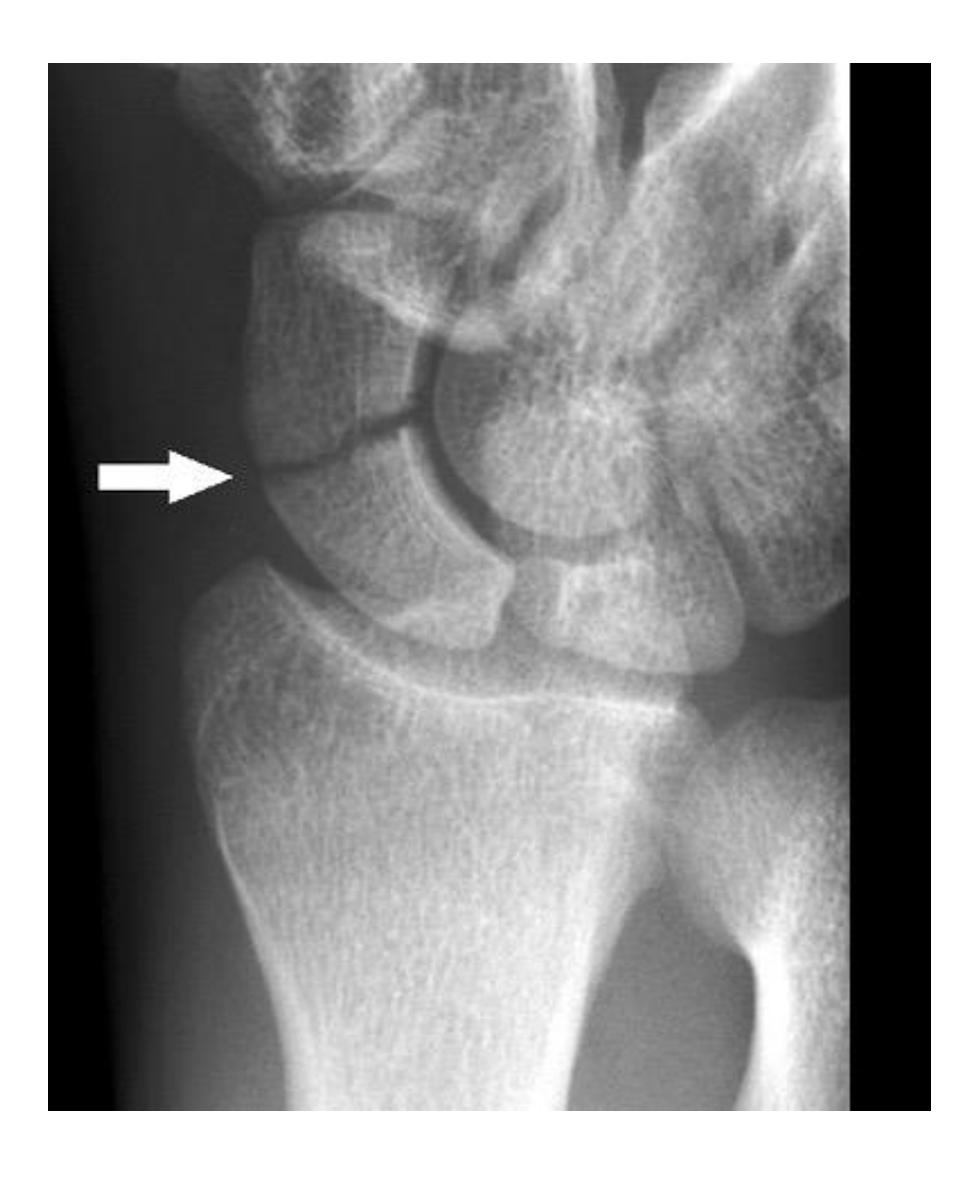

Management of imaging finding

What is the management of the finding in the image?

- Screw fixation

A 17-year-old male had a high ankle sprain followed by pain in his leg. X-ray films were obtained. According to the attached X-ray, which structure has been injured?

- B. Syndesmosis ligament

A 23-year-old male injured his ankle after a twisting ankle injury 2 days back. What is the most likely pathology based on shown x-ray?

Management Question: What is the management of the finding in the image?

- A. Screw fixation for syndesmosis injury

A 23-year-old male injured his ankle after a twisting ankle injury 2 days back. What is the most likely pathology based on the shown x-ray?

- Syndesmotic ligament injury